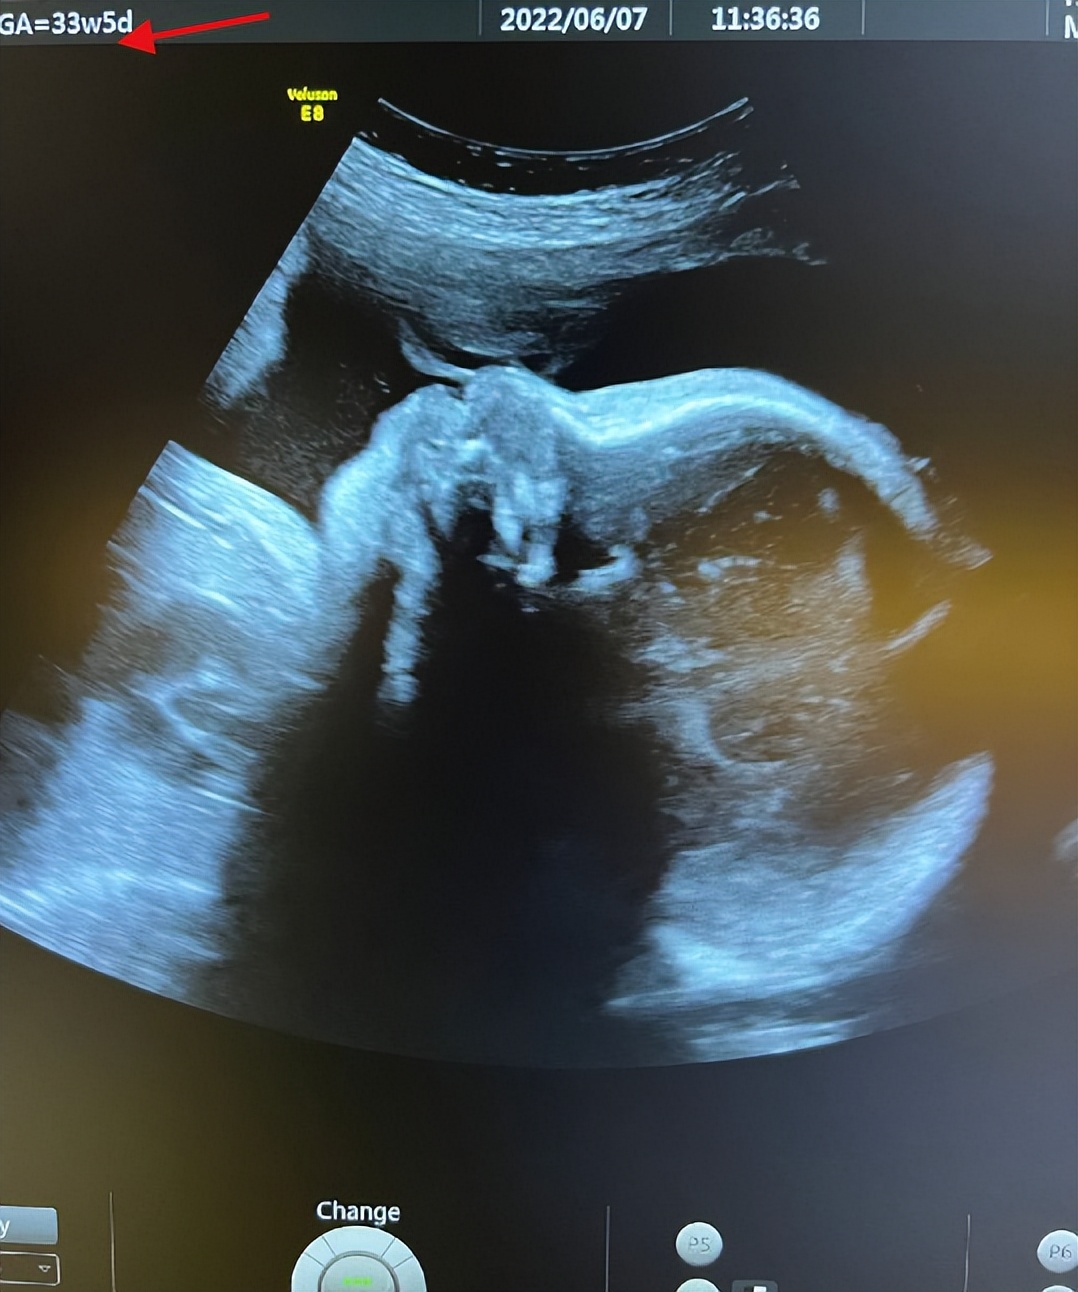

陈燃还分享出最新孕检B超照,从B超照来看,6月7日进行产检的陈燃,当时已经怀孕33周+5,进入孕晚期的她肚中宝宝基本已经成型,不过,如果不是专业人员,并不能通过这样一张B超照判定出宝宝性别, 那么问题来了,陈燃是通过何种手段知道肚中二胎宝宝性别的呢?